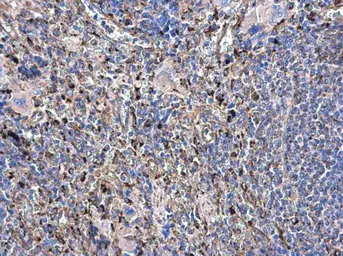

beta Tubulin antibody detects beta Tubulin protein at cytoplasm on human breast cancer by immunohistochemical analysis.

Sample: Paraffin-embedded breast cancer.

beta Tubulin antibody (GTX101279) dilution: 1:500.

Antigen Retrieval: Trilogy™ (EDTA based, pH 8.0) buffer, 15min

The data was published in the journal Cancer Metab in 2014. PMID: 25225614